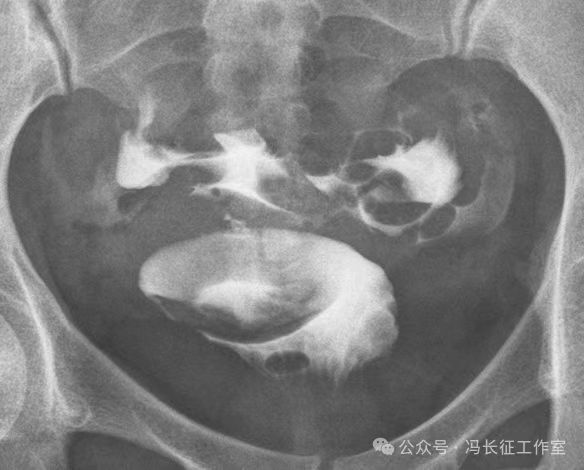

下面是一例正常子宫输卵管造影图(4张片)

微信图片_20240215160211.jpg